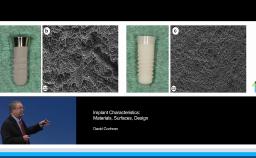

This lecture presents histomorphometric studies to demonstrate the strong relationship between bone and implant design, especially at the implant-abutment interface. The presenter shares key factors to explain the response of hard and soft tissue at the very first step of osseointegration. He focuses on the interaction between the design of the implant and the bone physiology. He develops the relationship between bone resorption and the inflammatory response of the host. The presenter also discusses different ways to decrease the inflammatory response at the implant-abutment interface. Supported by literature, a complete review of the various implant designs and their interactions with the bone is presented. The three major implant types are discussed: one-piece implant; two-piece implant with butt-joint interface; and two-piece implant with platform switching connection. This is a cutting edge lecture on the bone-implant relationship.

- discuss the advantages and disadvantages of the different implant designs in term of hard and soft tissue relationships